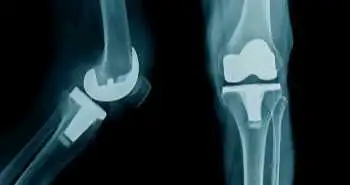

Оксфордська шкала оцінки функції колінних суглобів як незалежний прогностичний фактор досягнення максимального післяопераційного результату після тотального ендопротезування колінного суглоба

Використання Оксфордської шкали оцінки функції колінних суглобів (OKS) виявилася корисною для прогнозування досягнення максимального післяопераційного результату у пацієнтів з остеоартритом колінного суглоба, які перенесли первинне тотальне ендопротезування колінного суглоба.

Дослідження, опубліковане в журналі The Bone & Joint Journal, показало, що передопераційне значення OKS є незалежним прогностичним фактором досягнення максимального післяопераційного результату після проведення операції на коліні.

Аналіз проводили з метою визначити, чи вказує післяопераційне значення OKS на максимальний результат через 1 і / або 2 роки після проведення операції на коліні. Це дослідження також вивчало незалежні передопераційні прогностичні факторів у пацієнтів з остеоартритом колінного суглоба, які досягли найвищих показників або максимального результату після тотального ендопротезування колінного суглоба.